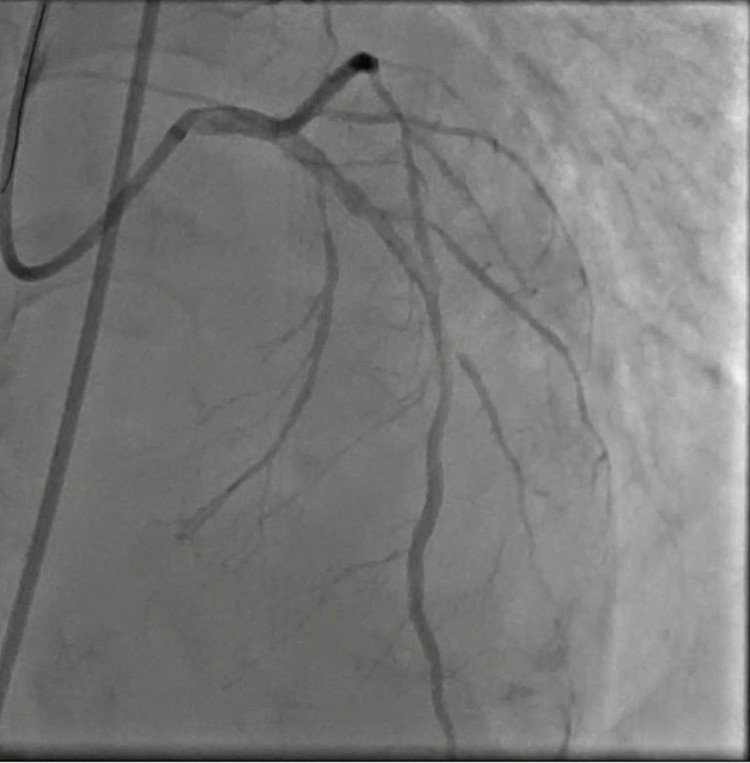

Với sự quyết tâm của gia đình, ekip can thiệp đã nhanh chóng tiến hành chụp, nong và đặt stent động mạch vành cho người bệnh. Quá trình can thiệp chụp DSA cho thấy người bệnh bị bệnh mạch vành 3 nhánh, hẹp nặng 70% – 80% nhánh bên phải từ đoạn gốc đến đoạn xa, hẹp 80% – 90% cả 2 nhánh bên trái.

Bệnh nhân được tiến hành đặt 2 stent cùng lúc vào 2 nhánh bên trái. Sau can thiệp tình trạng huyết động bệnh nhân dần ổn định, ngưng được thuốc vận mạch và rút ống thở sau 2 ngày điều trị tại Khoa Hồi Sức Tích Cực. Sau đó, bệnh nhân tỉnh táo hoàn toàn, không yếu liệt, không khó thở, không đau ngực, vận động gắng sức tốt và chuẩn bị có thể ra viện.

| Hình ảnh trước và sau can thiệp - Ảnh: BVCC |

Đặc biệt, người bệnh có tổn thương mạch máu khá đặc trưng của người bệnh đái tháo đường, đó là tổn thương cả ba nhánh mạch vành, kể cả tổn thương ở những mạch máu nhỏ kèm biến chứng phù phổi cấp. Do đó, ekip đã tiến hành can thiệp đồng thời 2 nhánh hẹp nặng nhánh liên thất trước và nhánh động mạch mũ để giải quyết tình trạng tắc nghẽn.